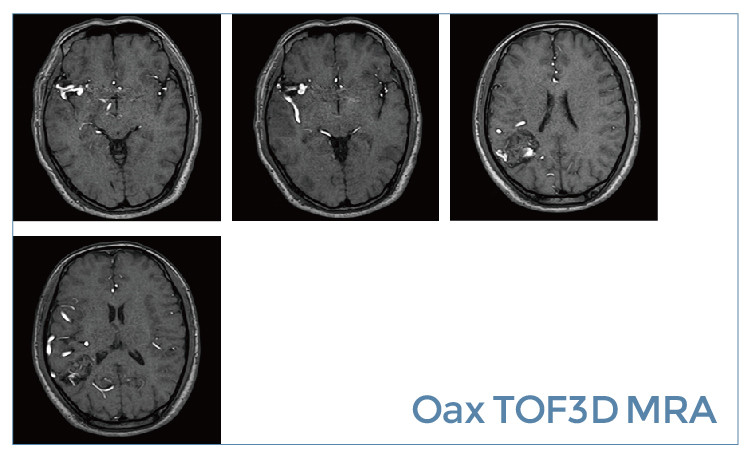

【朗润影像档案】20190531磁共振影像病例结果讨论